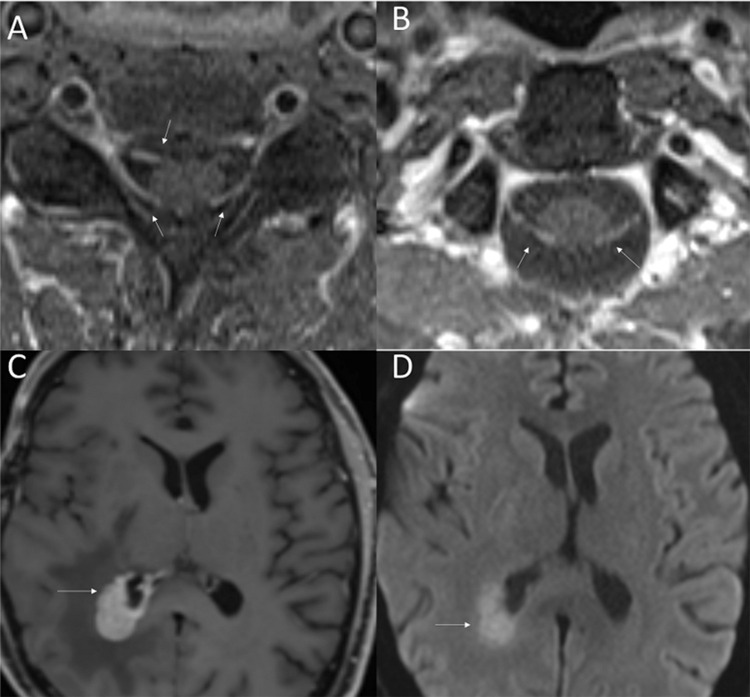

原发性颅神经淋巴瘤病(PCNL)是原发性中枢神经系统淋巴瘤(PCNSL)的一种罕见亚型,淋巴瘤浸润累及范围仅限于颅神经。在此,我们报告了一例成功进行基因组分析的 PCNL 病例。一名 57 岁的男性患者在诊断前经历了长达约 30 个月的漫长阶段,主要表现为通过类固醇治疗的多次颅神经痛。确诊时,患者右侧颅神经病变,累及颅神经(CN)V、VI 和 VII。右侧海绵状病变活检的病理结果与大 B 细胞淋巴瘤浸润神经纤维一致。患者的临床病程具有侵袭性和难治性,特点是病情无情发展,出现颈椎神经淋巴瘤病、脑脊液受累、脑外膜和脑实质内受累,尽管采用了多种疗法,包括化疗免疫疗法、布鲁顿酪氨酸激酶抑制剂、放射治疗、自体干细胞移植、嵌合抗原受体T细胞疗法(CAR-T)和全脑放射治疗。患者从最初诊断时起存活了22个月,在首次颅神经病变发作后存活了52个月。新一代测序发现了 PCNSL 中经常出现的突变(MYD88、CD79b 和 PIM1)。不寻常的发现包括涉及 PIM1 的总共 22 个突变,表明存在高度活跃的异常体细胞高突变和两个错义 CXCR4 突变。CXCR4突变从未在PCNSL中出现过,可能会对疾病生物学和治疗干预产生影响。我们通过文献综述来进一步阐明 PCNL。

Primary cranial neurolymphomatosis (PCNL) is a rare subtype of primary CNS lymphoma (PCNSL) in which infiltrative lymphomatous involvement is confined to cranial nerves. Here, we report a case of PCNL with successful genomic profiling. A 57-year-old male had a lengthy prediagnostic phase spanning approximately 30 months, characterized by multiple episodes of cranial neuropathies managed by steroids. At the time of diagnosis, the patient had right-sided cranial neuropathies involving cranial nerves (CN) V, VI, and VII. Pathological findings of the right cavernous lesion biopsy were consistent with large B-cell lymphoma-infiltrating nerve fibers. The clinical course was aggressive and refractory, characterized by relentless progression with the development of cervical spinal neurolymphomatosis, cerebrospinal fluid involvement, and ependymal and intraparenchymal cerebral involvement, despite multiple lines of therapy, including chemoimmunotherapy, Bruton's tyrosine kinase inhibitor, radiation, autologous stem cell transplant, chimeric antigen receptor T-cell therapy (CAR-T), and whole-brain radiation. The patient survived for 22 months from the time of the initial diagnosis and 52 months after the first episode of cranial neuropathy. Next-generation sequencing identified mutations (MYD88, CD79b, and PIM1) that are frequently observed in PCNSL. The unusual findings included a total of 22 mutations involving PIM1, indicating a highly active aberrant somatic hypermutation and two missense CXCR4 mutations. CXCR4 mutations have never been described in PCNSL and may have implications for disease biology and therapeutic interventions. We provide a literature review to further elucidate PCNL.